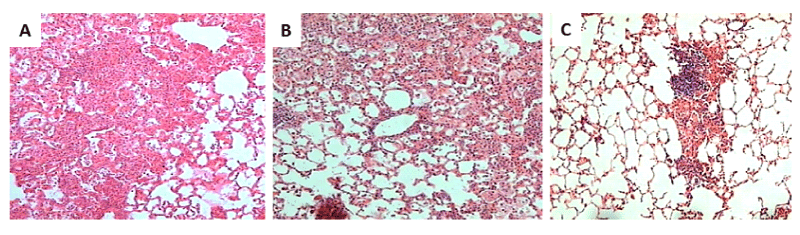

| Figure 7: Representative lung histopathology in non-vaccinated and vaccinated mice after 60 days of challenge with M. tuberculosis or M. bovis strains: A) Extensive areas of alveolar spaces are occupied by inflammatory cells corresponding to pneumonia in non-vaccinated animal infected by the intratracheal route with M. bovis AN5. B) Extensive lung consolidation is also observed in mutant mce-2A vaccinated mouse challenged with M. bovis AN5. C) In contrast, medium size patch of pneumonia is seen in mce-2A mutant vaccinated mouse challenged with M. tuberculosis H37Rv. (All figs 100x magnification, hematoxylin/eosine staining). |